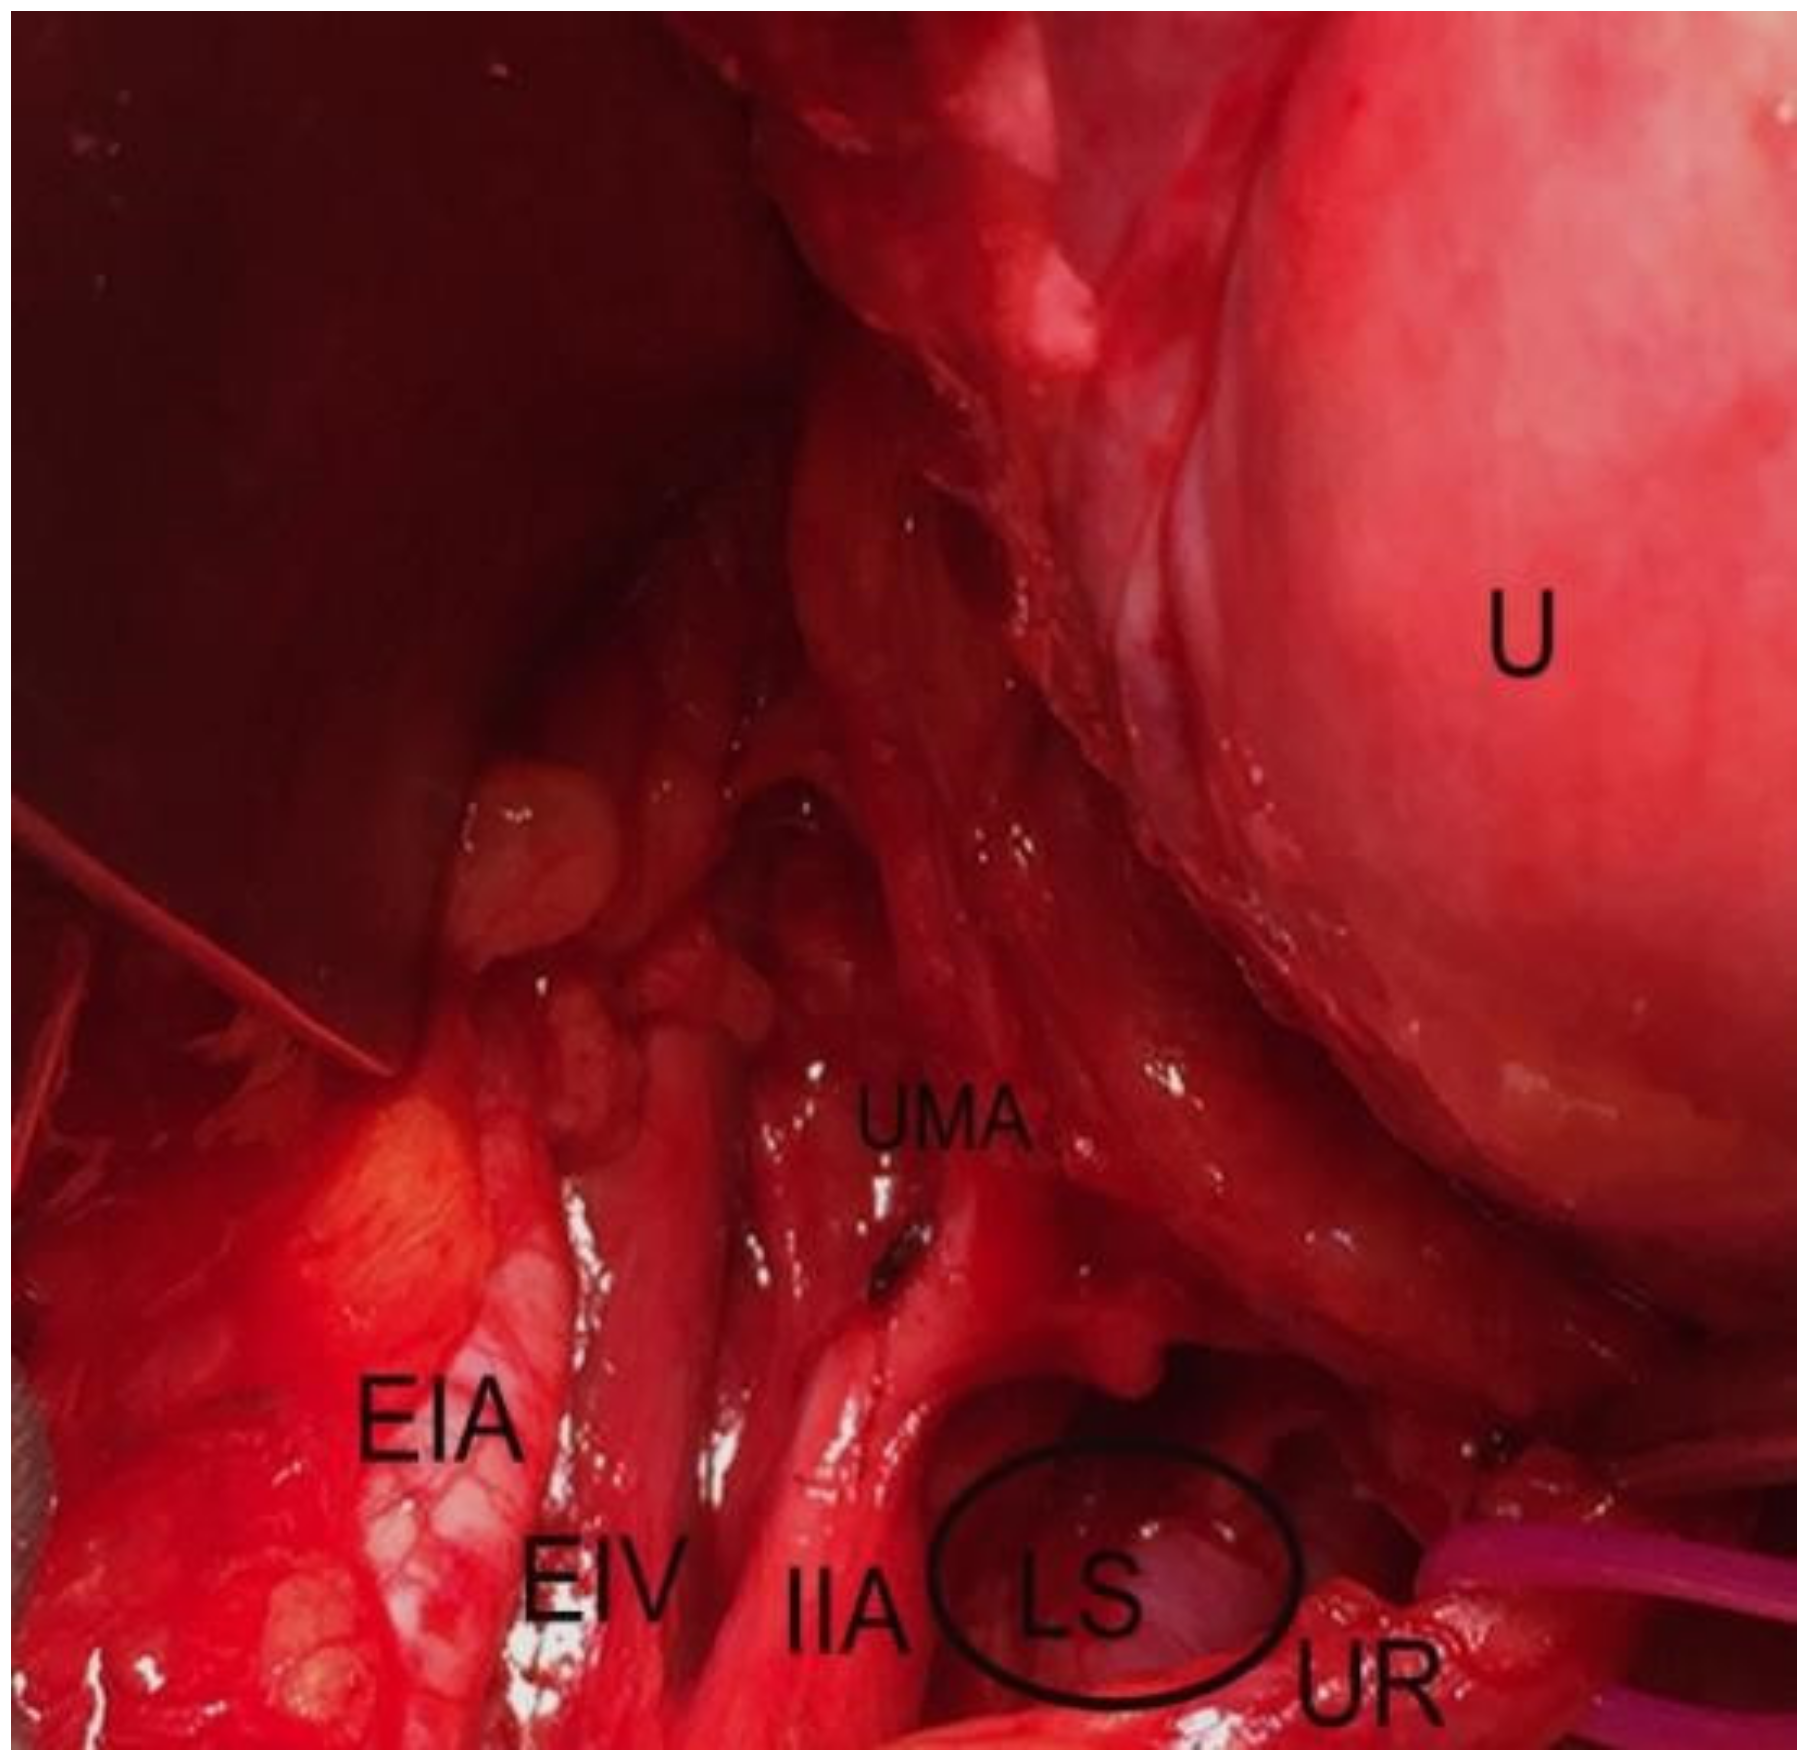

Pararectal space boundaries: ventrally–cardinal ligament, including the parametrium (over the ureter) and paracervix (below the ureter); dorsally–presacral fascia, sacrum; laterally–internal iliac artery; medially–rectum; cranially-peritoneum of the posterior leaf of the broad ligament; caudally-levator ani muscle [1,4,5,7,9,10,11]. There are two different approaches to the pararectal space–oncological (lateral) and endometriotic (medial), as reported by Puntambekar. In the lateral approach, the peritoneum is incised lateral to the infundibulopelvic ligament, whereas in the medial approach, the incision is medial to the infundibulopelvic ligament [7]. The first structure visualized through the medial approach is the ureter. After a slight dissection, the ureter divides the pararectal space (PRS) into medial (Okabayashi’s space) and lateral (Latzko’s space) pararectal spaces [5,7]. Lemos et al. reported that the hypogastric nerve is the structure dividing the PRS into lateral and medial [21].We agree with this proposal, as the ureter and the hypogastric nerve (HN) are in the same connective tissue plane (mesoureter), and the HN is localized 2–3 cm dorsally to the ureter [1,22] (Figure 6, Figure 7 and Figure 8).

Latzko’s space boundaries: ventrally-cardinal ligament; dorsally- presacral fascia, ventrolateral aspect of the sacrum, laterally-internal iliac artery (hypogastric artery); medially–ureter, mesoureter.

The incision is made in the peritoneum at the level of the pelvic brim after transperioneal identification of the ureter, remaining parallel and lateral to the ureter. Development of this space starts at the level of iliac vessels’ bifurcation. Latzko’s space is exposed through craniocaudal and dorsoventral dissection between the internal iliac artery and the ureter [1,4,5,7,9,23].

In gynecology/oncogynecology, Latzko’s space is developed during pelvic lymphadenectomy or in cases requiring access to the pelvic splanchnic nerves, inferior hypogastric plexus (pelvic plexus). The dissection of Latzko’s space exposes the uterine artery originating from the internal iliac artery. The procedure is performed for various cases—radical hysterectomy, adhesions from previous pelvic surgeries, large myomatous uterus, temporary ligation with clips for abdominal, laparoscopic hysterectomy or myomectomy [7,9]. Although it is not necessary, the approach for this procedure starts with transection of the round ligament. The posterior leaf of the broad ligament is incised laterally to the infundibulopelvic ligament. After identifying the ureter and internal iliac artery, the dissection proceeds caudally between these two landmarks and leads to the uterine artery originating from the hypogastric artery [24].

In obstetrics and gynecology, Latzko’s space is developed during internal iliac artery ligation to control pelvic hemorrhage. The peritoneum overlying the psoas muscle is incised 8-9 cm parallel to the external iliac artery and lateral in the line with the ureter. Further dissection exposes common iliac artery, bifurcation of the internal iliac artery, and the internal iliac vein. The Latzko’s space is then opened next for identification and medialization of the ureter, along with lateralization of the internal iliac artery [25]. A right angle forceps is passed between the internal iliac artery and vein distal to the posterior division of the artery (in a majority of cases superior gluteal, lateral sacral, and lumbosacral arteries), which supply the buttocks and gluteal muscles [1]. The artery is ligated with a non-absorbable suture. Complications such as external or common iliac artery ligation, internal iliac vein or ureter injury, buttock claudication or pelvic ischemia might occur [1,17,25].

Figure 8. Latzko’s space dissected by open surgery (left side of the pelvis). U—uterus; UMA— umbilical artery; IIA—internal iliac artery; EIV—external iliac artery; EIV—external iliac vein, UR— ureter; LS—Latzko’s space.